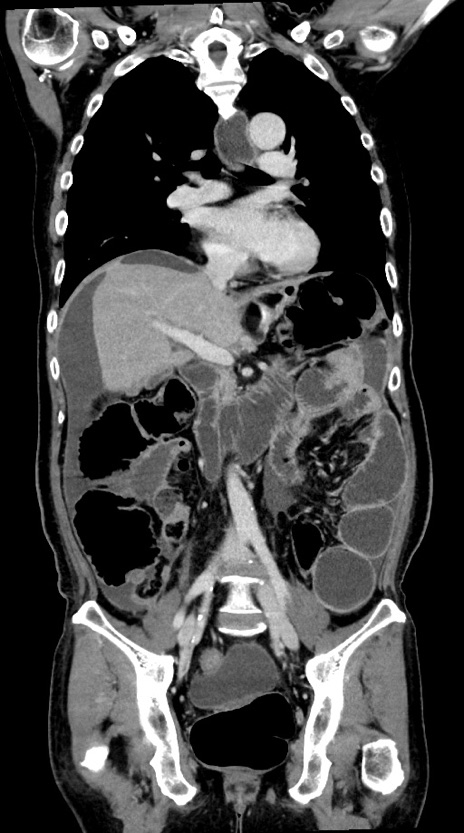

症例28(冠状断像)

横断像

【症例】60歳代男性

【主訴】嘔吐

【現病歴】胃癌にて胃全摘後。食思不振が悪化し、夜中に嘔吐することがある。

【既往歴】胃癌、胃全摘、脾摘、胆摘後

【データ】WBC 5900、CRP 10.56